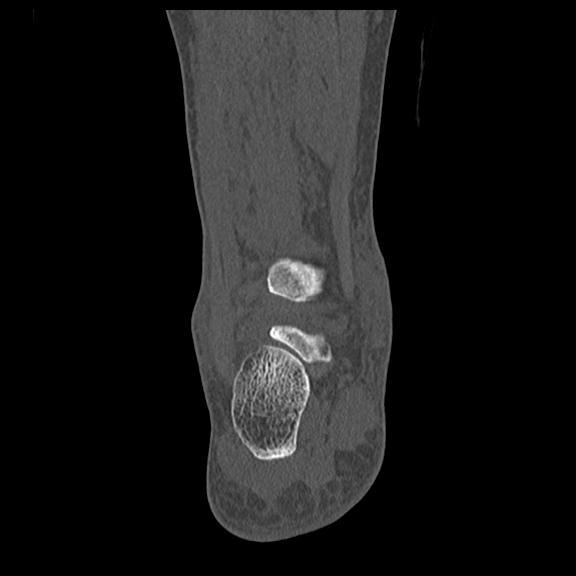

102755 1/4 2R 1/15 2R 右足関節 68歳女性 右三果脱臼骨折